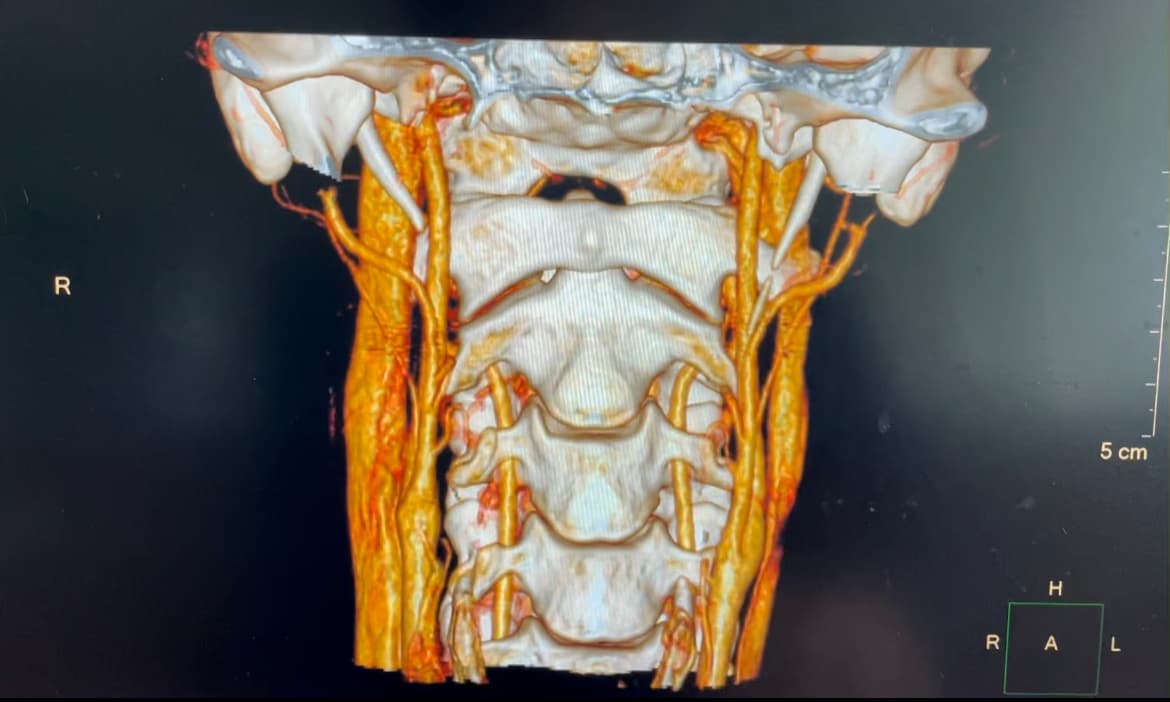

I pointed out a weird dark area near/in my IJV I can’t tell if it’s artifact, clot, or something else compressing it. And I also have a little stenosis on my right lower side of my IJV. If anyone has any info or opinions don’t be scared to let me know.

Have you seen anything about scalene or neck muscle problems? I get great benefit from relaxing my right shoulder/neck area. And when I palpate that area I find My muscles are super tight and I have a few areas that feel like like a Guitar string it is so tight. I wonder if that could have been the reason that kicked off my symptoms when I was doing pull ups. You can see I have stenosis on the right side near the area of a lot of muscles.